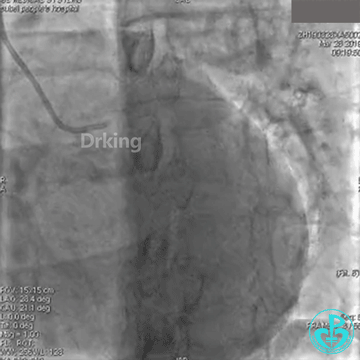

此时反复看造影图,发现LCX有一支高位的小的OM,预想是否可以把导丝送至高位OM远段,再用双腔微导管辅助支撑下将另一根导丝通过严重扭曲处送至LCX远段呢?

以下是导丝成功通过严重扭曲病变的图:

把Sion导丝送至高位OM的远段,在双腔微导管的辅助支撑下,把BMW导丝通过LCX扭曲及病变处顺利送至远段,撤出双腔微导管,2.0×20mm球囊对病变处PTCA后狭窄减轻,于病变处植入2.75×23mm支架一枚,后分别用2.75×12mm、3.0×12mm球囊对支架内后扩,复查造影原病变处狭窄消失,TIMI血流三级。